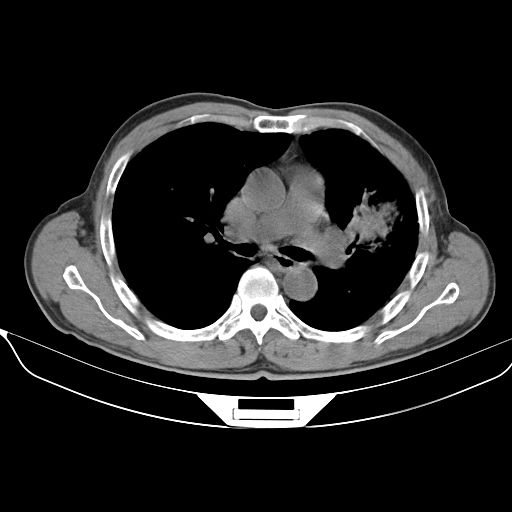

以下是引用心路寻觅在2010-3-1 10:23:00的发言:[br]1、考虑左肺上叶周围型肺癌[br]2、右上肺陈旧性病灶。[br][br][本贴已被 心路寻觅 于 2010-3-1 10:40:18 修改过]

以下是引用shuiyuan在2010-3-1 10:45:00的发言:[br]考虑左肺上叶中心型肺癌伴阻塞型炎症,邻近胸膜受侵。